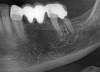

bilal Опубликовано 16 июля, 2013 Поделиться Опубликовано 16 июля, 2013 Пациентка, около 50 лет. Хочет поставить импланты в 3 квадрате. Думаю поставить 2 импланта: в области 3.4 и 3.6, и между ними поставить мост. Снимок до удаления 3.6 и моста. 3.3 - под коронкой сейчас. КТ пока не готов.В области 3.6 объем кости позволяет поставить имплант 5*11,но в зоне 3.4 рассасалась кость по горизонтали, по вертикали - достаточно кости.Срок лечения ограничен в связи с переездом пациента.Помогите пож-та, с выбором сроков проведения аугментации в области 3.4:1- сначала провести аугментацию графтом под мембраной и отсроченно поставить имплант;2- поставить имплант и в ходе операции положить графт под мембрану.Приложил фото со схемой лечения на фото альвеолярного отростка пациента. Ссылка на комментарий